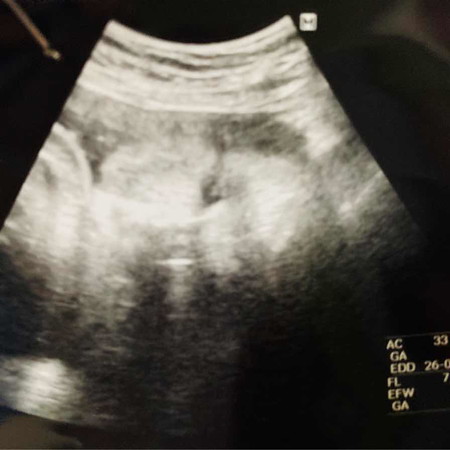

แม่ท้อง